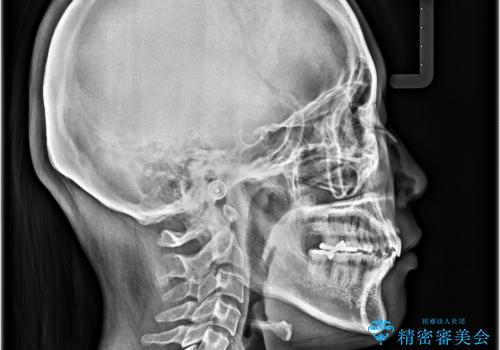

- 上の前歯が出っ歯と突出した口元を気にして来院された患者様です。

上顎歯列全体が前方に飛び出している印象であったので、上顎左右の第一小臼歯2本を抜歯し、ワイヤー装置にて抜歯矯正を行うこととしました。

骨格的に上顎が前方にあり、上顎のみの抜歯矯正のため、期間はかかることが予想されましたが、スムーズに移動してくれたおかげで、2年弱の短期間で終えることができました。